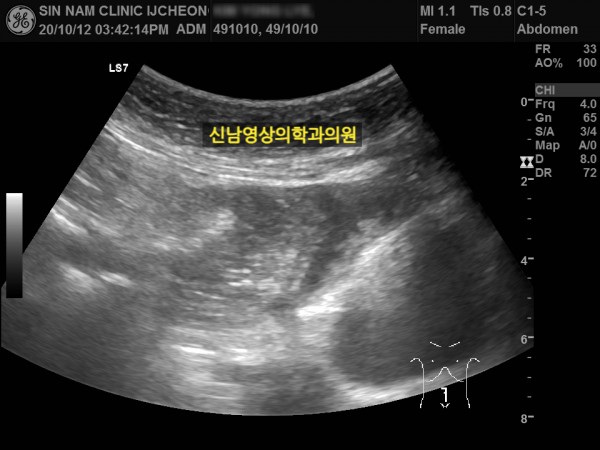

본 환자분께서는 사흘 정도 지속되는 복통과 고열로 내원하신 60대 중반의 환자분입니다.

복통 부위의 병변을 확인하기 위해서 복부 촬영과 복부 초음파검사를 진행했고, 맹장은 이상이 없고, 대장 주위로 복강삼출액(물)이 둘러싸고 있으면서 상행대장부위의 부종이 심하게 발견되었습니다.

원내 피검사상 백혈구 수치가 높아 대학병원 응급실로 전원 조치하고 응급수술을 받으셨고...